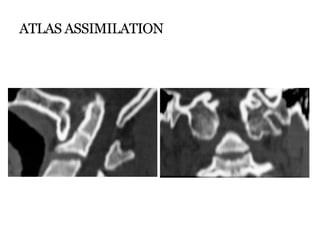

ATLAS ASSIMILATION

 Represents most cephalic

‘blocked vertebra’

 0.25% of population

 Usually occurs in

association with other

anomalies such as BI and

Klippel Feil syndrome.

 Associated with

segmentation failures

b/w C2-3 : atlanto-axial

subluxation in 50%.